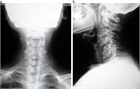

1. 頚髄症と腰部脊柱管狭窄症合併例では、頚椎手術を優先するが、腰部脊柱管狭窄症が主訴となっている場合には頚椎が伸展しないように術中体位に十分注意する。